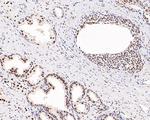

Androgen Receptor Monoclonal Antibody (AN1-15)

WB IHC (P) IHC (F) ICC/IF IP GS

Androgen Receptor Recombinant Rabbit Monoclonal Antibody (10G4D3)

WB IHC (P) ICC/IF ELISA IP